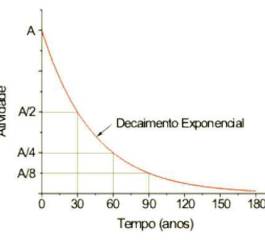

Meia Vida de Elementos Radioativos. Entenda Mais Sobre Meia Vida